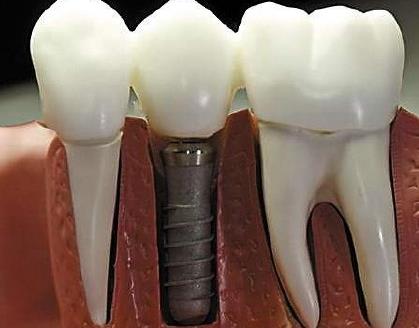

深圳牙科醫院醫生解答,一般種植牙是沒有年齡限製,無論是中成年人,還是老年人都是可以做種植牙的,但是未成年人是不可以的,這是適應症要求。種植牙的使用證要求,還有如果是高齡老人,需要排查全身疾病,比如說糖尿病、高血壓、腦血管病、心髒病等,需要控製在一定範圍內(nei) ,才能酌情考慮。

但是比起中年人,老年人要麽(me) 是因為(wei) 長期不修複牙齒缺失,要麽(me) 是長期佩戴活動假牙,導致牙齦萎縮、牙槽骨吸收嚴(yan) 重,所以有的老年人牙槽骨骨量不夠,想要做種植牙,是需要做植骨手術的;如果是有嚴(yan) 重牙周炎的,也需要及時治療,控製在一定範圍。